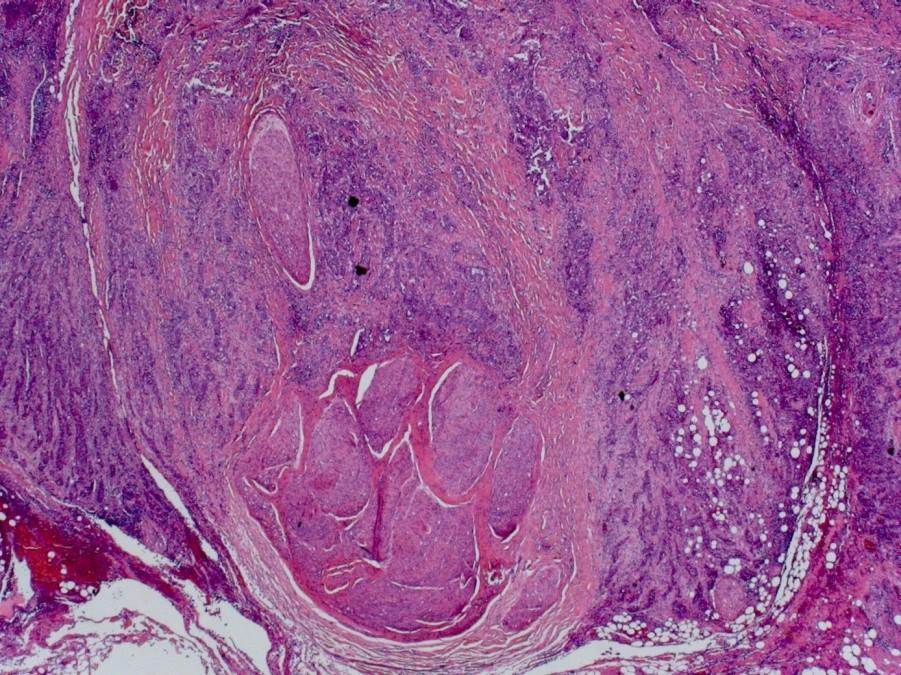

Adenoid cystic carcinoma

 Wide age range

 Slow growing with tendency for perineural spread

 Tubular, cribriform and solid patterns

 2 cell populations: ductal cells and abluminal myoepithelial cells

 Cytologically bland, angular and dense chromatin

 Cribriform pattern: multiple punched out holes “pseudocysts”

 Contain dense eosinophilic basement membrane-like material or bluish mucopolysaccharides

 Perineural invasion +++

 5 yr survival good, 20 yrs <10%

 Lung metastases seen later in course